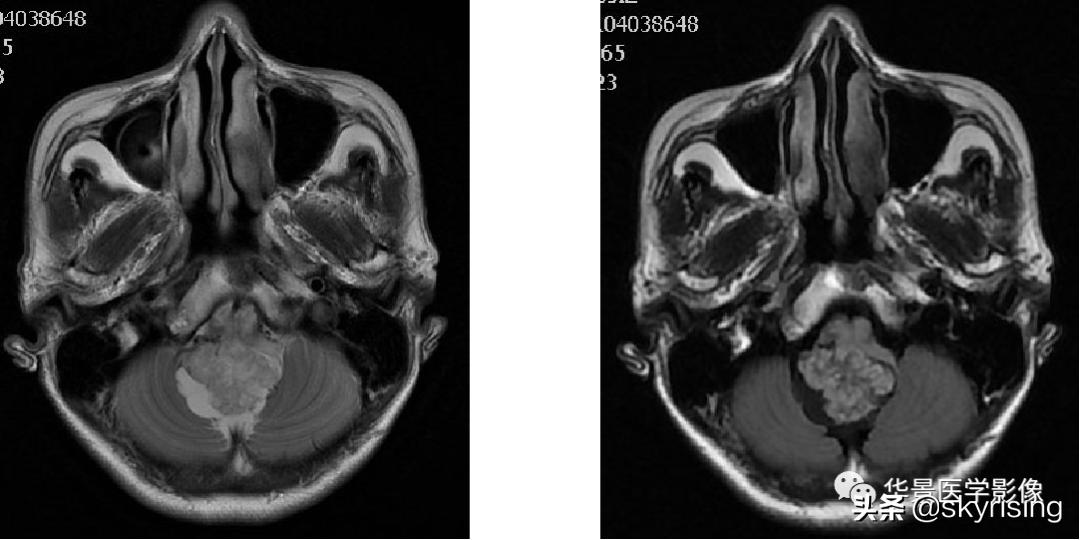

以下依次为T2WI、FLAIR、T1WI、增强、DWI及ADC:

上图白色箭头:小脑延髓池内延髓背侧不规则形团块影,不均长T2信号,FLAIR条片样信号减低,提示水分子含量高。

蓝色箭头:注意病灶与延髓边界不清,不除外来源或侵及延髓。

黄色箭头:右侧细小流空血管信号;左侧较粗大贴边流空信号血管影。